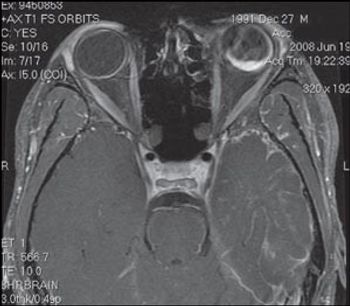

Choroidal hemorrhage in the left orbit with retinal detachment: your dx?